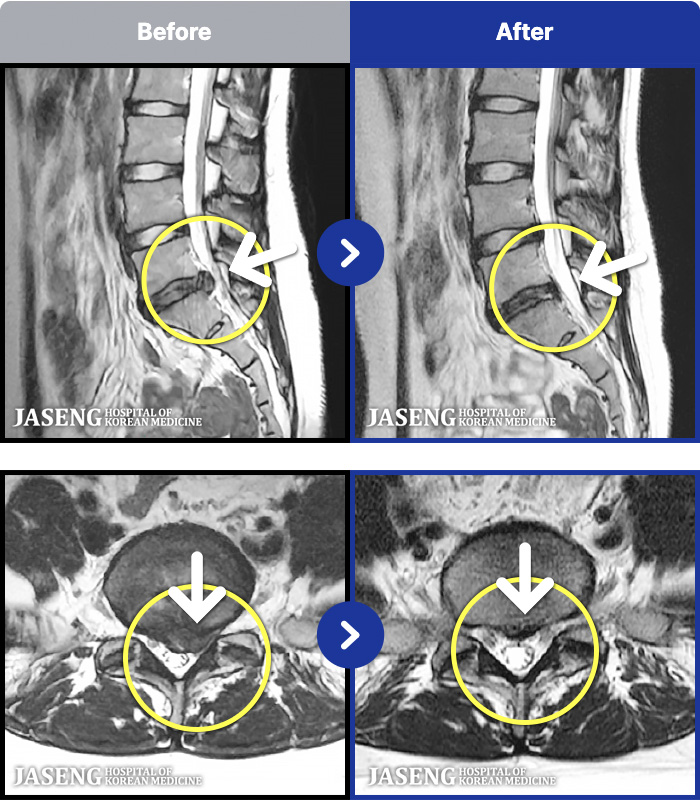

[ϻ] 24.07.25~25.08.01

ȯںп Ǹ ǿ ԿǾ, ο ġ ۿ Ƿ ġḦ Ͻñ ٶϴ.